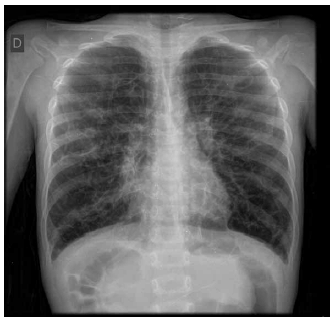

Considere as imagens e a seguinte descrição: menino, com cinco anos de idade, com piora lenta e progressiva de falta de ar há mais de um ano e piorando no último mês, impossibilitando-o de brincar.

O diagnóstico mais provável é: